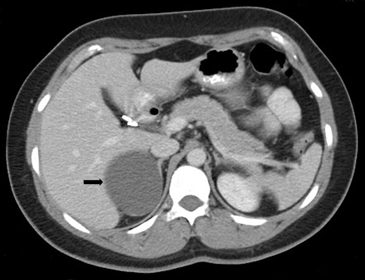

Figura 6. Lesión homogénea, de contornos bien delimitados (flecha) visualizada en tomografía computada sin contraste realizada en contexto de estudio de diseminación de cáncer mamario. A pesar de los caracteres morfológicos aparentemente benignos, se demostró que la lesión correspondía a una localización secundaria.

BLos márgenes de la lesión pueden ser una característica útil, los contornos irregulares se asocian a una mayor probabilidad de malignidad. Sin embargo, las metástasis, especialmente si son pequeñas, pueden presentar una morfología muy similar a la de un adenoma (Figura 6), vale decir homogéneas y de bordes bien delimitados. Se ha descrito también que la preservación de la morfología adreniforme usualmente se asocia a benignidad (Figura 7 a y b).